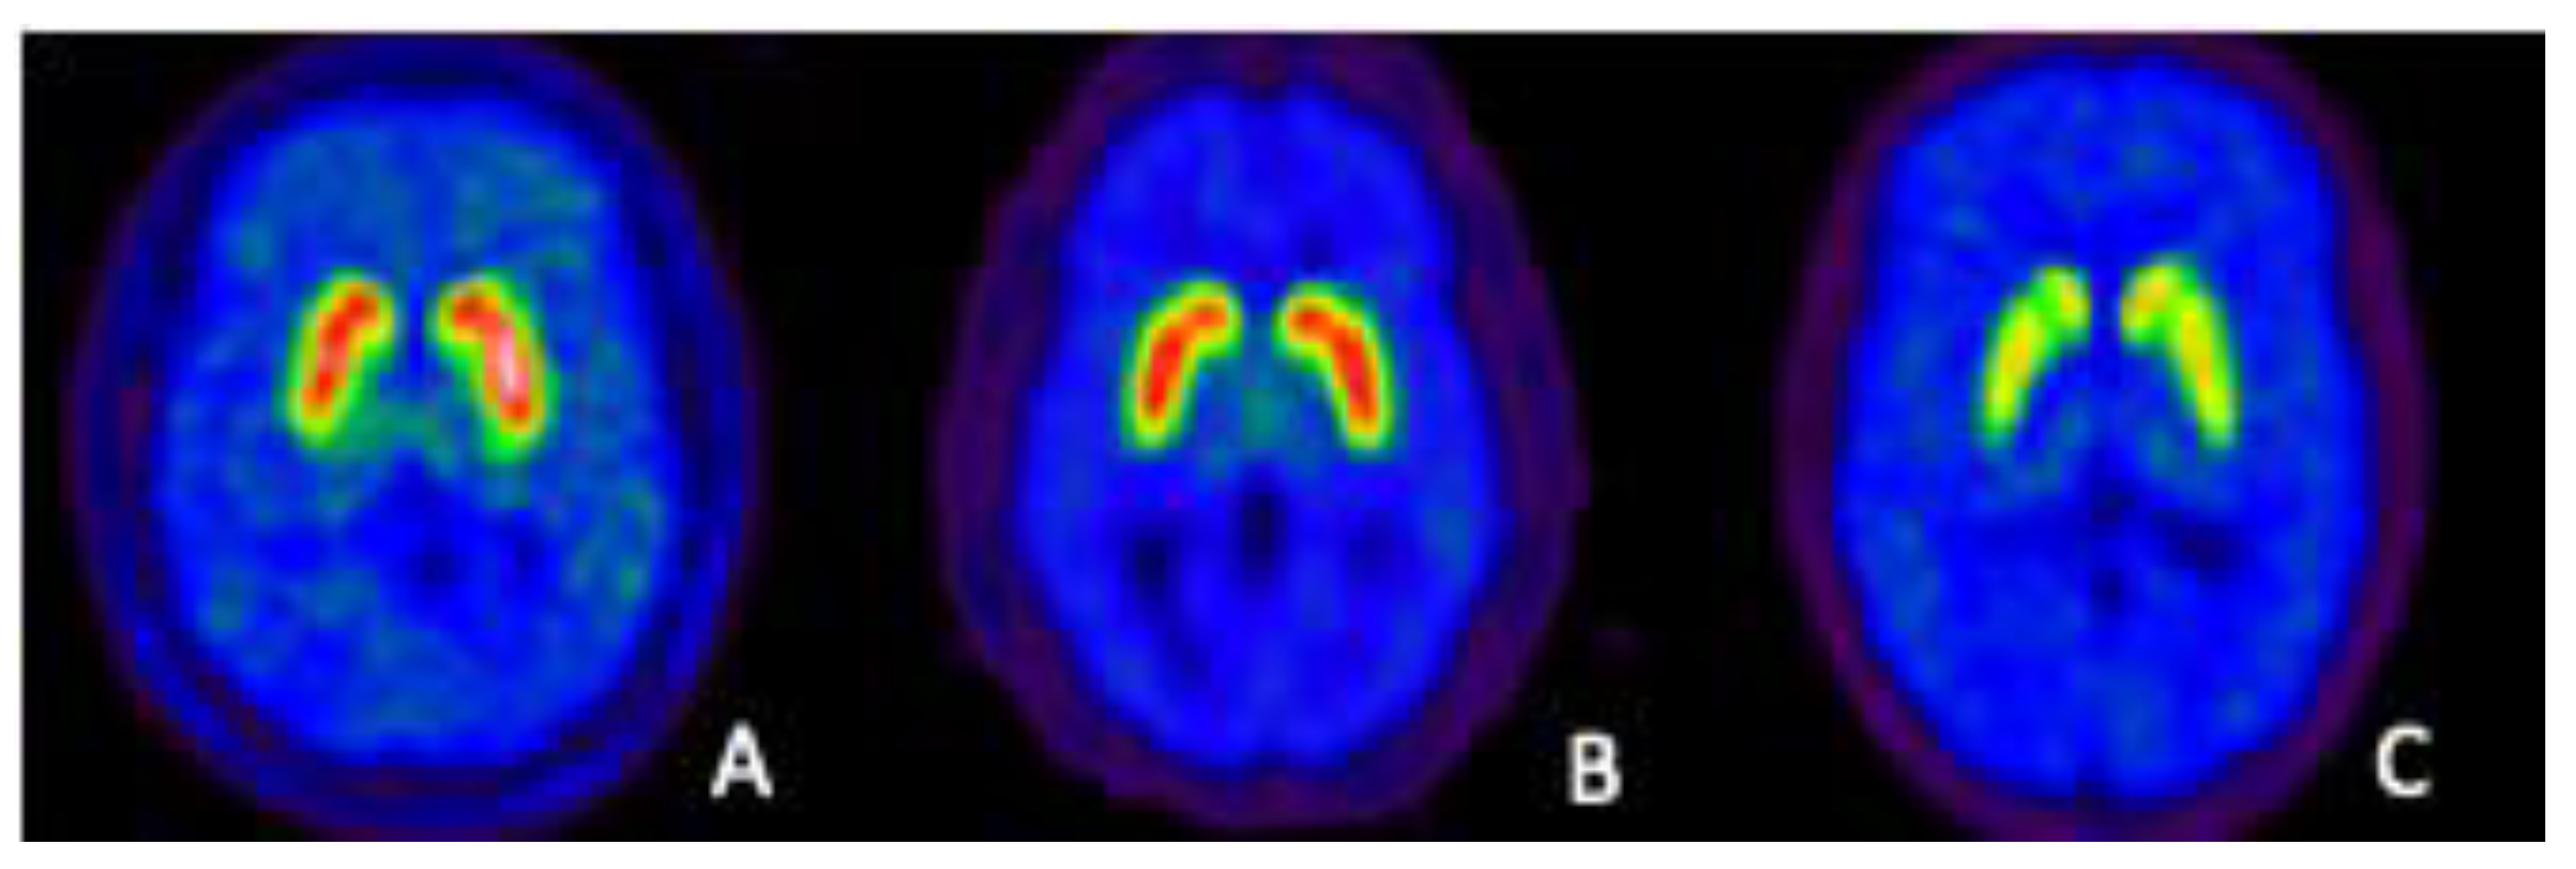

6. Neuronal Membrane Dopamine Transporters (DAT)

Imaging of the DAT: Current and Future Applications